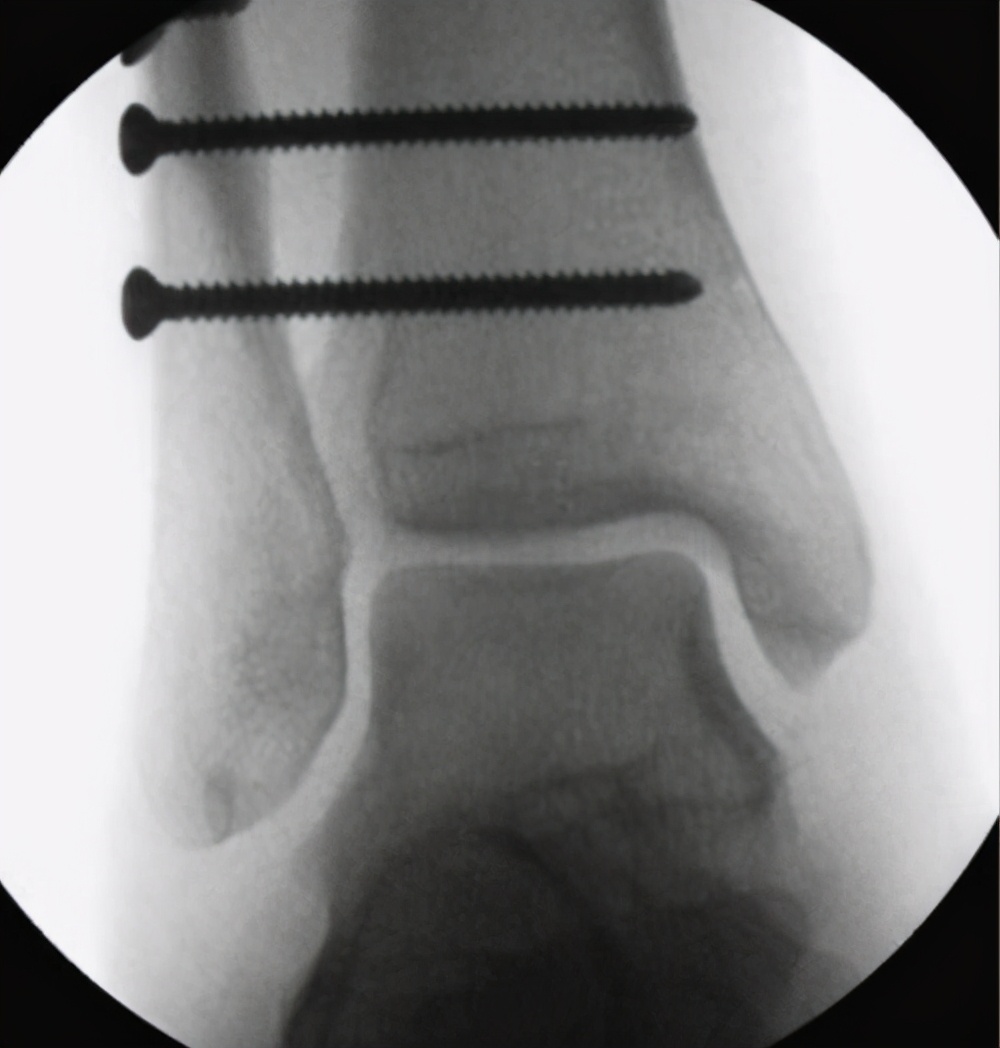

2、特殊部位:踝关节的下胫腓联合螺钉,一般术后6-8周,在下地负重前一定要取掉,否则下地后容易导致螺钉断裂;这是因为什么呢?因为这里的钉子太容易发生断裂了,如果不及时取出的话,一旦断裂,想 在 取出那就难了,事后可能引发关节炎,严重影响生活。

下胫腓联合螺钉